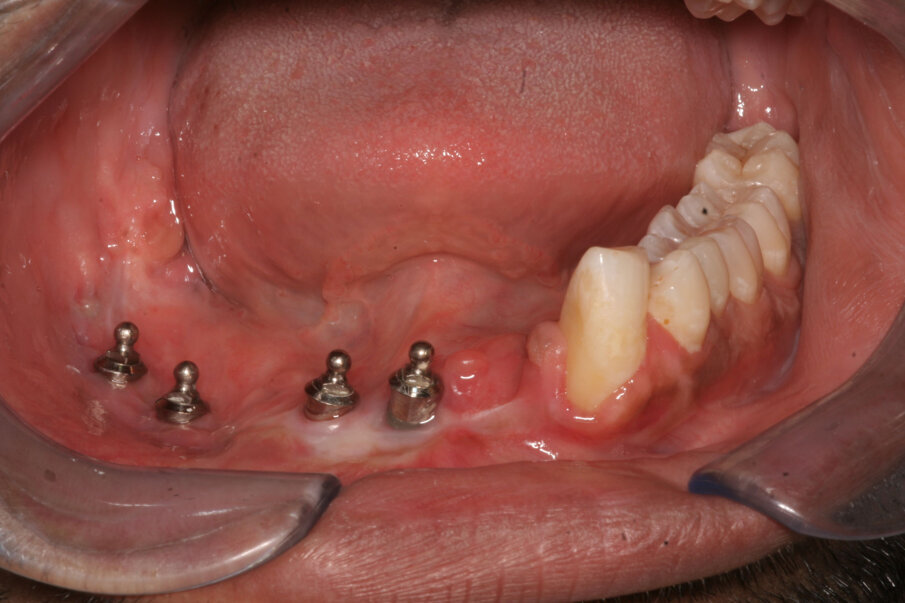

Fig 3: Clinical intraoral picture of the same patient. Note the presence of healthy keratinised mucosa around implants in the mandible reconstructed by the free fibula flap.

Denture Guided Epithelial Regeneration is a technique that recreates peri-implant keratinized mucosa in free flap reconstructed jaws. We now have more than a hundred cases with follow-ups of up to 10 years, showing the success of this technique (Figure 1- 3). Moreover, our proteomic studies involving mass spectrometry and immunohistochemical methods have demonstrated that the regenerated mucosa functionally resembles keratinized oral mucosa.